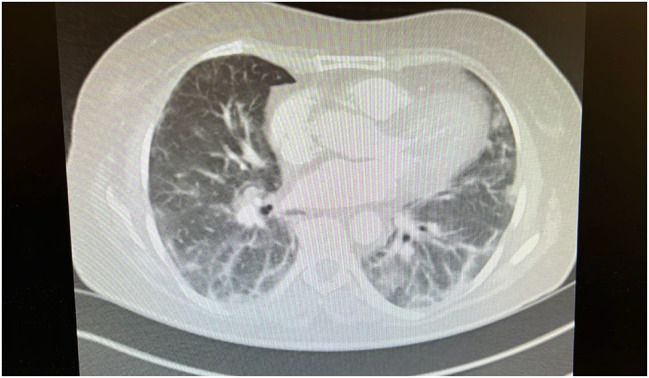

Anti-synthetase syndrome is a rare autoimmune disorder characterised by the presence of autoantibodies against aminoacyl transfer RNA synthetases. We report a unique case of a 54-year-old woman with anti-OJ anti-synthetase syndrome, characterised by the atypical occurrence of digital vasculitis in conjunction with the classic manifestations of anti-synthetase syndrome. Our patient presented with digital vasculitis affecting the right third and fourth fingers, rapidly evolving interstitial lung disease of the organising pneumonia subtype, sub-clinical myositis, arthritis and mechanic's hands. Notably, she had no prior history of Raynaud's phenomenon. Serological tests revealed positive anti-OJ antibodies and weakly positive anti-MI2 antibodies. Our patient's condition was managed with intravenous methylprednisolone then after stepped down to prednisolone and mycophenolate mofetil with successful therapeutic response.Current literature primarily highlights Raynaud's phenomenon and vasculopathy-related ischemia, whether occlusive or non-occlusive in anti-synthetase syndrome. This case study identifies digital vasculitis as a distinctive complication of anti-synthetase syndrome, anti-OJ subtype. It emphasises the importance of recognising vascular complications, including vasculitis, even when classic signs like Raynaud's phenomenon are absent. Further research is crucial to fully understand the range of vascular manifestations associated with anti-synthetase syndrome.